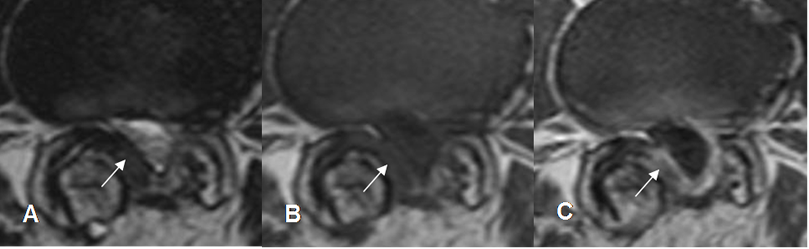

Fig 123. Fibrosis postquirúrgica.

A: RM axial en T2 y B: RM axial en T1. Imagen hipointensa en el receso lateral del lado derecho, que oblitera la grasa y desplaza las raíces.

C: RM axial en T1 con contraste. La imagen realza de forma homogénea, correspondiendo a fibrosis.